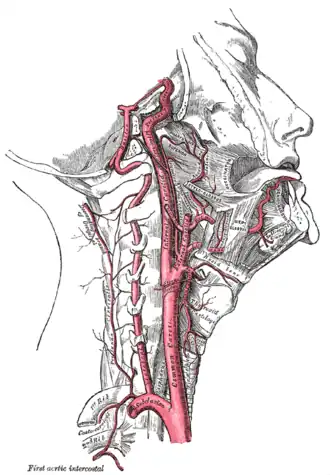

Strangling involves one or several mechanisms that interfere with the normal flow of oxygen into the brain:[3][4]

- Compression of the carotid arteries or jugular veins—causing cerebral ischemia.

- Compression of the laryngopharynx, larynx, or trachea—causing asphyxia.

- Stimulation of the carotid sinus reflex—causing bradycardia, hypotension, or both.

Depending on the particular method of strangulation, one or several of these typically occur in combination; vascular obstruction is usually the main mechanism.[5] Complete obstruction of blood flow to the brain is associated with irreversible neurological damage and death,[6] but during strangulation there is still unimpeded blood flow in the vertebral arteries.[7] Estimates have been made that significant occlusion of the carotid arteries and jugular veins occurs with a pressure of around 3.4 N/cm2 (4.9 psi), while the trachea demands six times more at approximately 22 N/cm2 (32 psi).[8]

As in all cases of strangulation, the rapidity of death can be affected by the susceptibility to carotid sinus stimulation.[5] Carotid sinus reflex death is sometimes considered a mechanism of death in cases of strangulation, but it remains highly disputed.[3][9] The reported time from application to unconsciousness varies from 7-14 seconds if effectively applied [10] to one minute in other cases, with death occurring minutes after unconsciousness.[3]